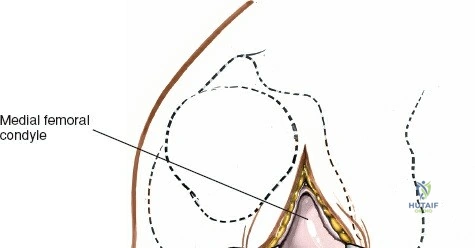

The medial meniscus is a C-shaped, semilunar fibrocartilaginous structure that resides on the medial tibial plateau, acting as an interface between the femoral condyle and the tibial plateau. It is broader posteriorly than anteriorly.

Open Medial Meniscectomy – The Specific Approach

The open medial meniscectomy, once the standard, is now reserved for scenarios where arthroscopy is unavailable, technically infeasible (e.g., severe arthrofibrosis, large foreign bodies, or specific revision surgeries), or for very large, difficult-to-manage loose bodies. The seed content heavily focuses on this approach.

- Landmarks: Palpate the medial joint line, medial epicondyle of the femur, and medial tibial plateau. The saphenous vein and nerve courses superficial and posterior to the medial femoral condyle, requiring careful attention.

Exposure of the Meniscus:

- Retractors are carefully placed to expose the medial tibiofemoral compartment. Self-retaining retractors may be used, but care must be taken to protect the articular cartilage.

- To improve visualization, the knee is brought into hyperflexion (as per seed content, "beyond a right angle"). This maneuver, combined with external rotation of the tibia and a valgus stress applied to the knee, widens the medial compartment. This allows for improved access to the posterior horn of the medial meniscus.